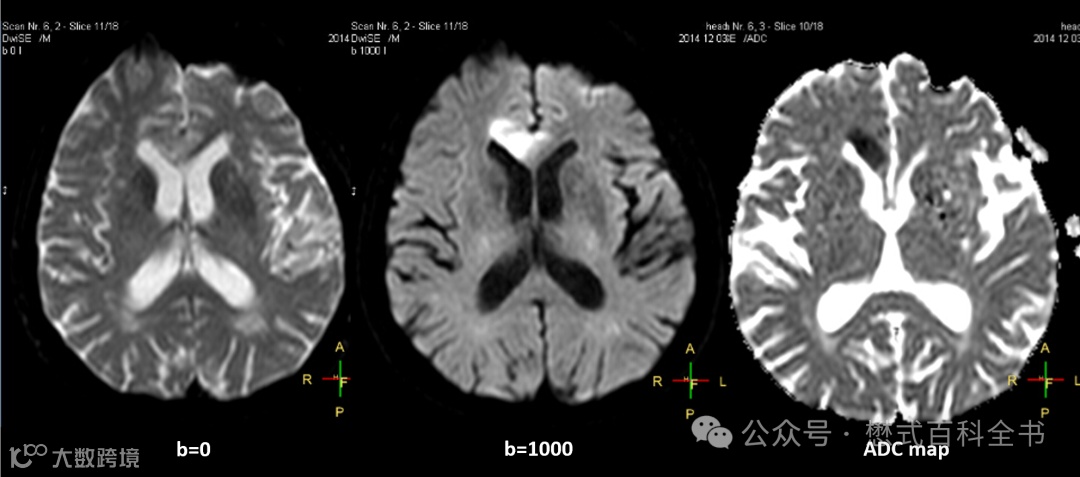

图4所示,是一个头颅常规的DWI序列,扫描两个b值,b=0和b=1000,然后计算一个ADC图。

其中,b=0的图,大家可以发现,脑脊液是高信号(亮的),灰白质对比也和常规T2WI类似。这个图像可以等效地理解为EPI采集的T2*WI,它的对比度或者权重就是T2或者T2*。

图7是DWI图像的对比度权重。如果b值越大,则DWI的权重越大。如果b值越小,比如极端情况下,b=0,那么这个b=0的DWI理论上权重就不含Diffusion,只含T2或T2*权重。从权重这一点来说,DWI中b=0的权重和常规T2WI权重都是T2(或T2*)。